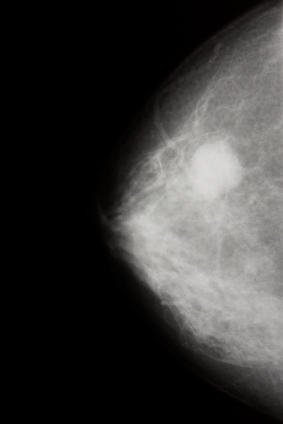

Фиброаденома молочной железы  —  доброкачественная опухоль молочной железы, происходящая из клеток самой железы, возникающая на фоне гормонального нарушения.  Является разновидностью узловой мастопатии.

Чаще всего встречается обычная фиброаденома не перерождающаяся в рак или саркому. Реже встречается быстрорастущая филлоидная (листовидная) фиброаденома, как правило больших размеров, которая может перерождаться в саркому.

В молочной железе прощупывается безболезненное опухолевидное образование размером от 0,2 см до 7см, гладкое, плотное,  смещающееся при ощупывании.

В диагностике фиброаденом используется маммография (рентгеновское исследование молочной железы), УЗИ, пункция (биопсия) и осмотр маммолога.